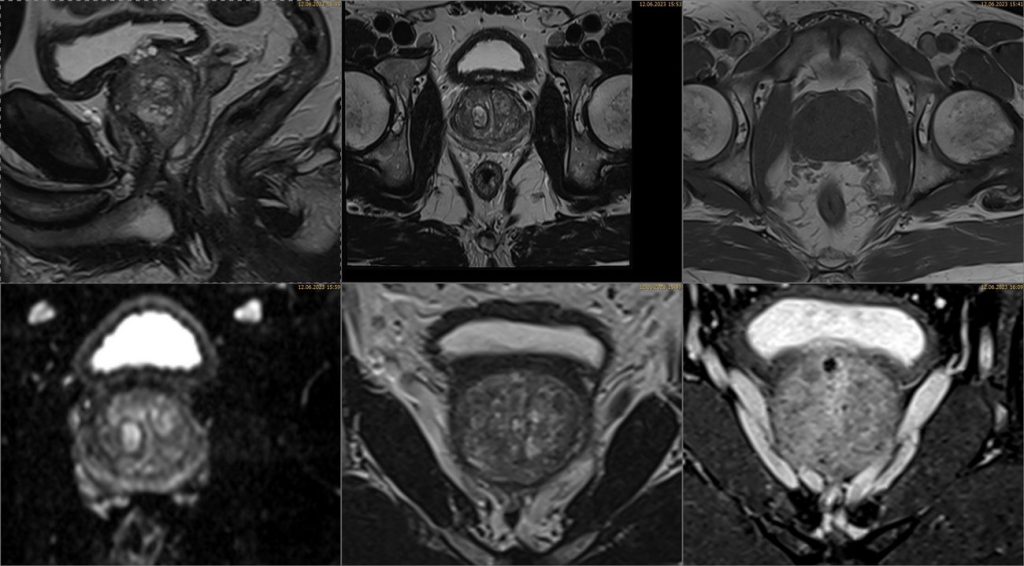

Prostata MRT